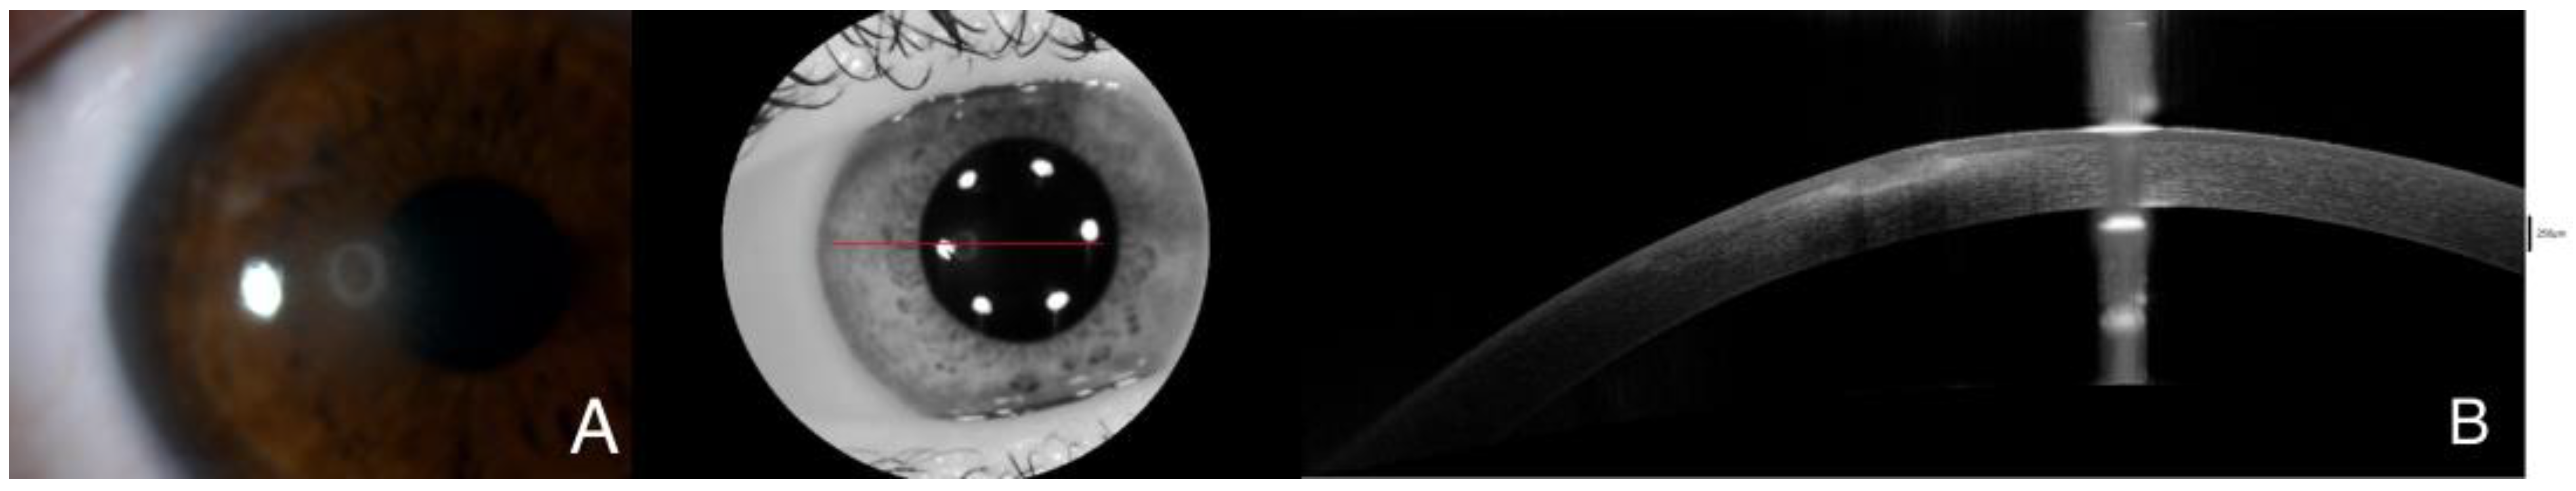

Figure 1.

Slit-lamp examination demonstrates a 3 × 3 mm paracentral ulcer affecting epithelium and anterior stroma with 2 mm perilesional infiltrate. No signs of inflammation were identified on the anterior chamber (A). Initially, AS-OCT displayed Bowman layer disruption with stromal and epithelial edema, along with stromal hyperreflectivity, which may indicate an inflammatory process taking place (B). A corneal scrapping sample for microbiologic cultures was obtained and the patient started receiving hourly fortified topical treatment with Vancomycin and ceftazidime, along with topical voriconazole every two hours and ciprofloxacin ointment once a day. The best corrected visual acuity in that moment was 0.6 in the right eye. The red line is correspondene of the en face picture with the selected section on the AS-OCT.